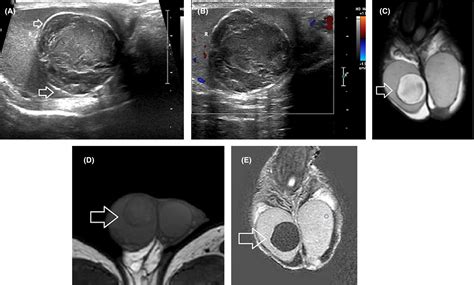

• Ultrasound: An ultrasound can help determine the nature of the lump and rule out more serious conditions like testicular cancer.